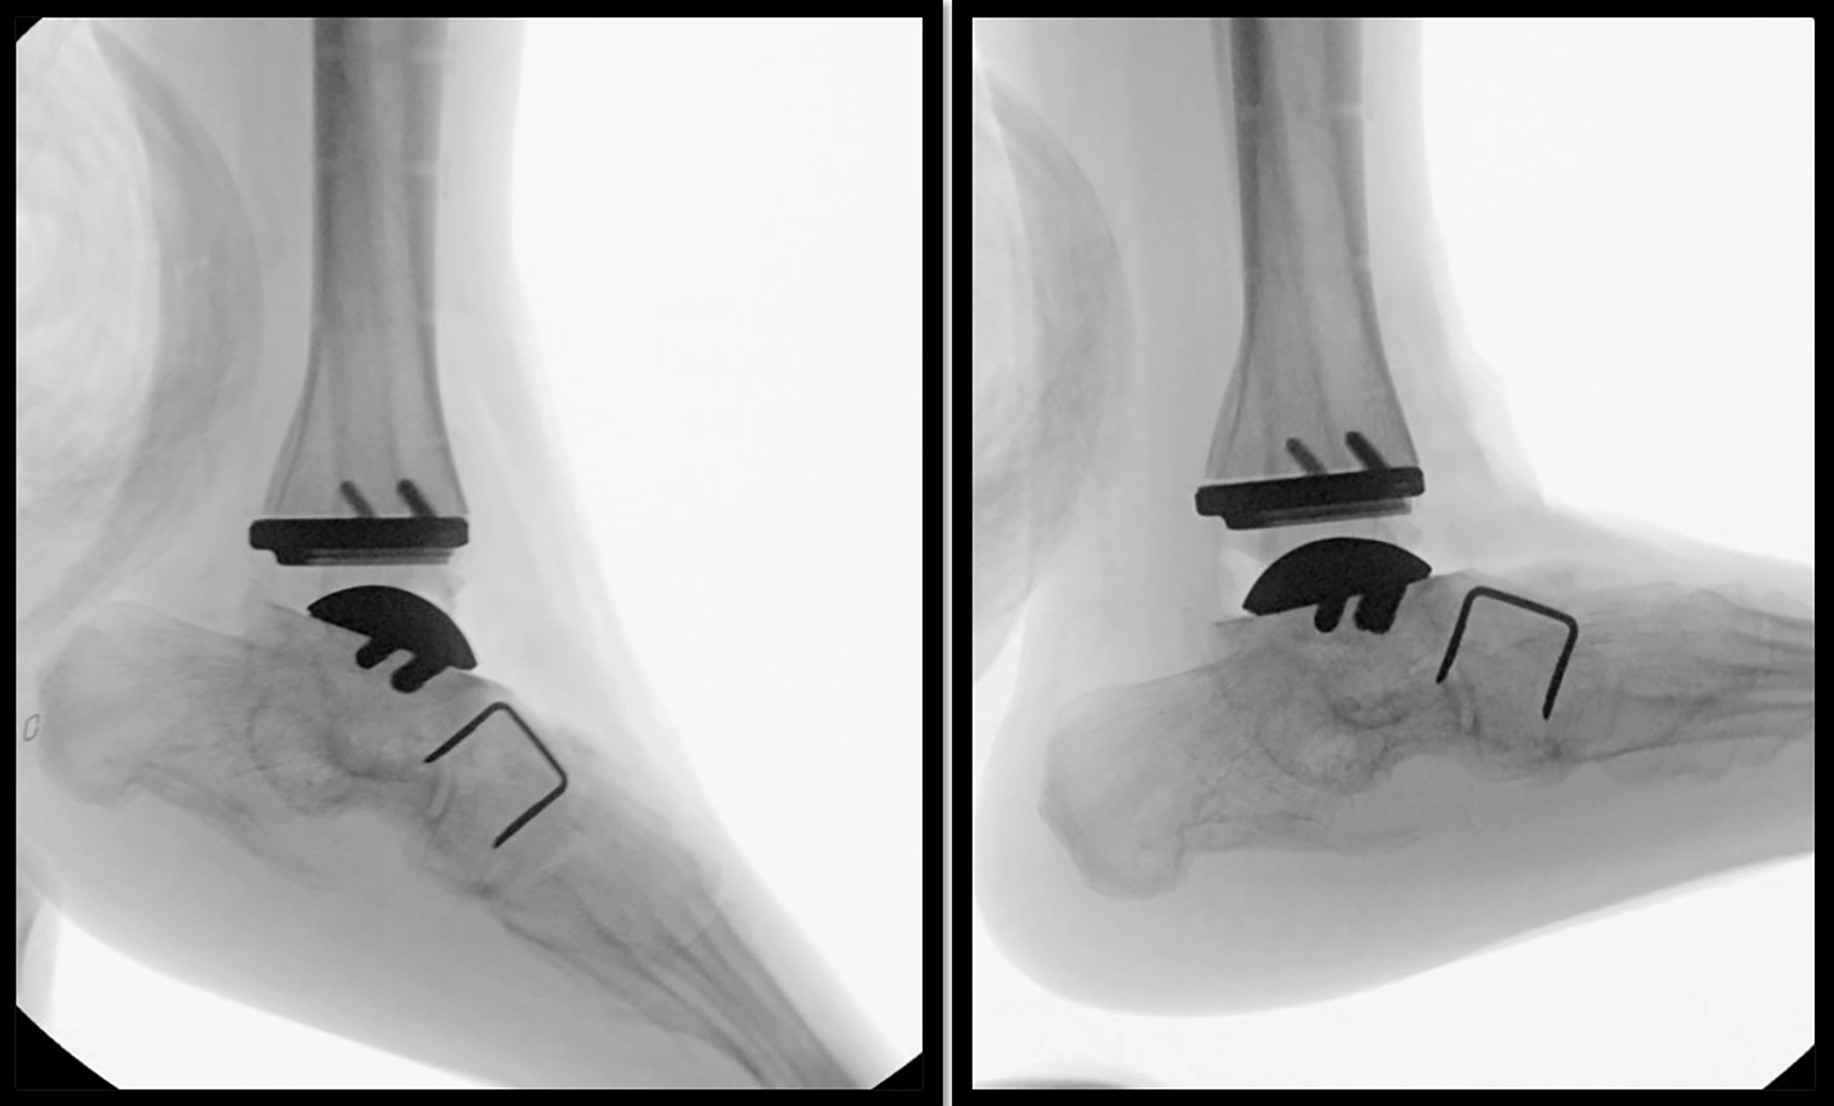

The alternative to the fusion procedure is a total ankle replacement. Like other total joints, an ankle replacement prosthesis consists of three parts: two metal components – one on either side of the joint — with a thick plastic central component. This allows for maintained ankle joint motion and a more normal walking pattern compared to the arthrodesis procedure. There are many varieties of total ankle replacement implant available. Consult with your surgeon to determine the best implant option for you.